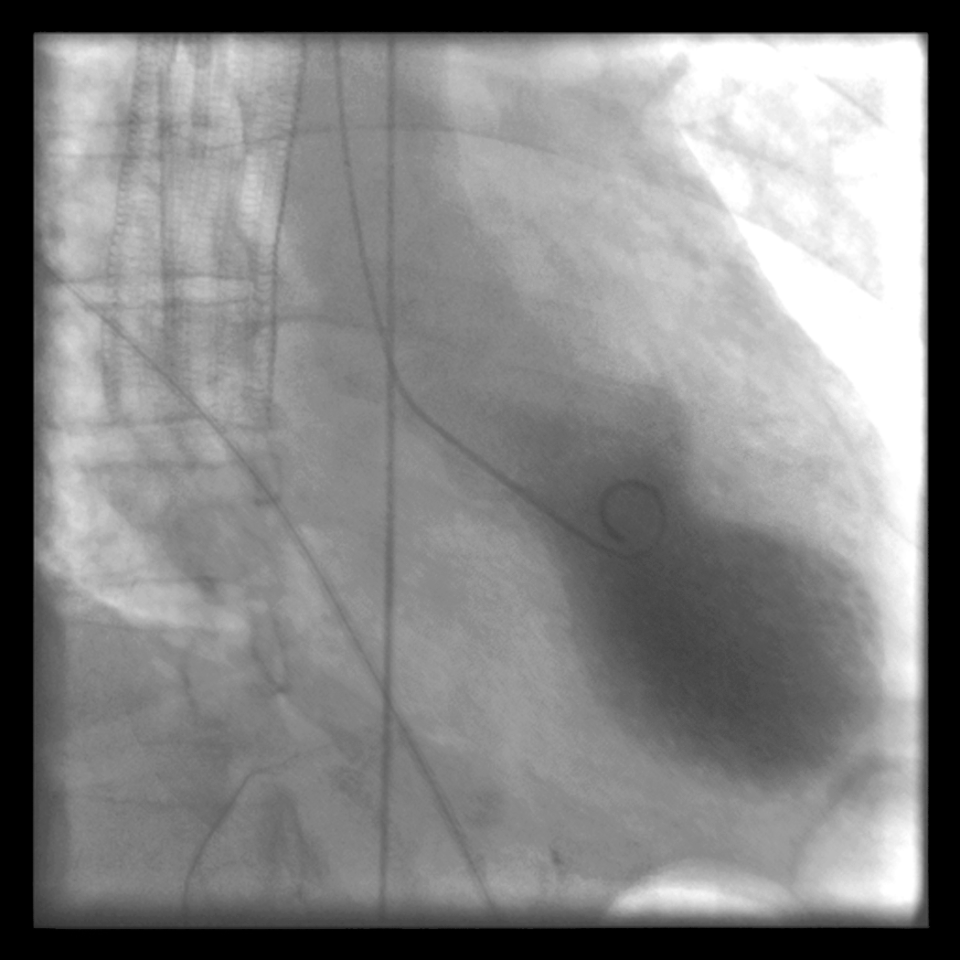

Апикальное баллонирование при синдроме разбитого сердца — вентрикулография - nicetry.blog

Апикальное баллонирование при синдроме разбитого сердца — вентрикулография. (Автор(ы): Tara C. Gangadhar и соавт., Journal of Medical Case Reports)

Название «такоцубо» придумал японский врач Хикару Сато: на снимках сердце похоже на керамический горшок для ловли осьминогов — узкая верхняя часть и расширение внизу. Симптомы напоминают инфаркт, но обычно коронарные артерии не перекрыты критически. Поэтому при внезапной боли в груди алгоритм один: вызвать скорую и исключить инфаркт.